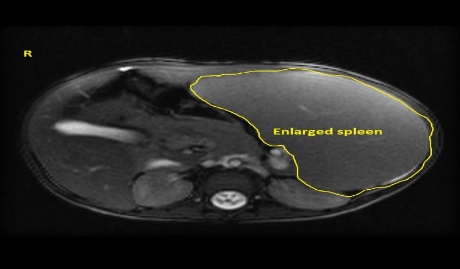

Imaging studies (ultrasound, CT scan, MRI)

Ultrasonography, computed tomography, and magnetic resonance cholangiopancreatography are three noninvasive imaging techniques for people with jaundice. Ultrasonography or computed tomography is typically the first-line option for evaluating blockage, cirrhosis, and vascular patency, with ultrasonography being the least intrusive and most cost-effective method. Magnetic resonance cholangiopancreatography or endoscopic retrograde cholangio- pancreatography can be used to see the intra- and extrahepatic biliary tree further, with the latter allowing for treatment options such as biliary stent implantation to ease blockage. Endoscopic ultrasonography, in conjunction with endoscopic retrograde cholangiopancreato- graphy, can evaluate common bile duct blockages and distinguish between a mass and a stone.

Fig 3. Mri